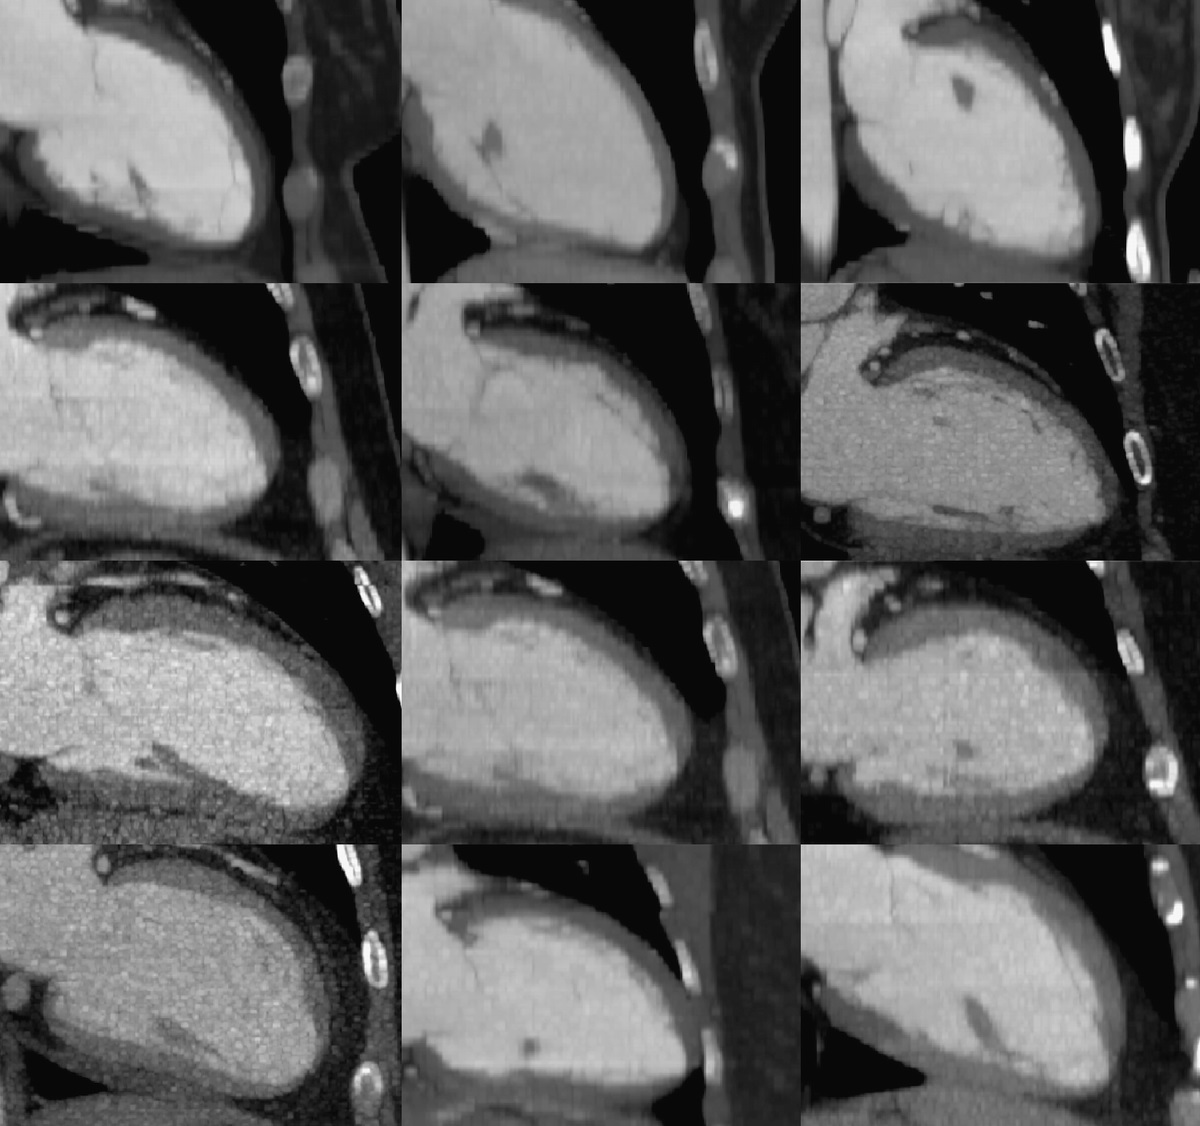

Fabrys

https://www-sciencedirect-com.proxy1.lib.uwo.ca/science/article/pii/S0894731718300415?via%3Dihub#bib20

• Binary Sign: "hyperechogenic endocardial surface adjacent to a relatively hypoechogenic subendocardial layer"

Non-Compaction

• Multiple criteria exist

• Jenni:

• Thick non-compacted and thin compacted layer (>2:1)

• Flow in the intertrabeculated recess

• Prominent trabecular mesh